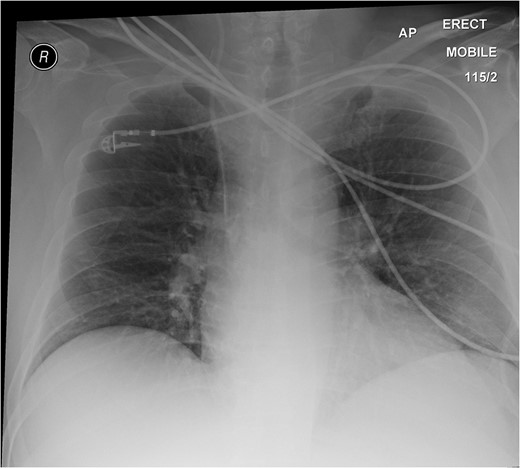

A 59-year-old man presented with a 12-h history of sudden onset of right upper quadrant and epigastric pain. The pain was then felt localized to the right iliac fossa and was constant, made worse with movement. Although he felt nauseous, he had not vomited. His last bowel movement which was 1 day previously had been normal with no bleeding per rectum noted, and no lower urinary tract symptoms.

On physical examination, he was pyrexial at 38.4°C, tachycardic with a pulse rate of 120 beats per minute, tachypnoeic at a respiratory rate of 20 per minute and a blood pressure of 130/70 mmHg. Clinically, he appeared flushed and in pain. His abdomen was not distended but tender and guarding in the right upper and lower quadrants. Right flank tenderness was also elicited. There were no hernias and his chest was clear.

Meckel's diverticulum is rare and accounts for only 2% of the general population. An equal incidence is found in men and women. Meckel's diverticulitis is one of the recognized complications of the condition and is clinically indistinguishable from appendicitis, except that the pain and tenderness typically localized at the periumbilical region. Progress of the diverticulitis may lead to perforation and peritonitis. A fistula between Meckel's diverticulum and the appendix has also been reported [1].

The learning point of this clinical vignette is that Meckel's diverticulitis is often clinically indistinguishable from appendicitis especially in adult patients. Computed tomography (CT) has become an invaluable tool for the evaluation of abdominal pain. CT scanning is useful in demonstrating acutely inflamed diverticula, typically identified as a blind pouch off the distal small intestine and associated with bowel wall thickening and in detecting the presence of enterocolic and enterovesical fistulas.